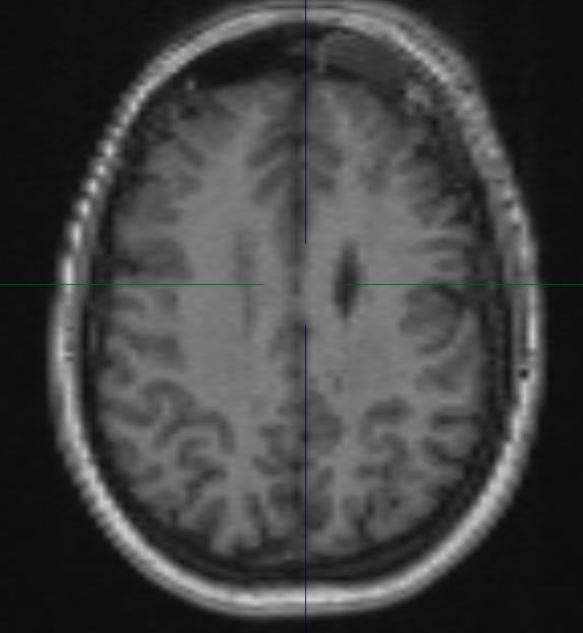

The structural correlates of the above EEG findings appear below. There is enlargement of the left-ventricular system, atrophy of the head, body and tail of the caudate nucleus and the left hemisphere appears modestly smaller in size than the right, most evident on axial sequences. The MRI was done while the patient was quite restless. As you can see from these pictures, the left occipital cortex and the left thalamus do not demonstrate any structural correlate to the asymmetry of alpha rhythms. However, we know from the EEG that the left hemisphere is markedly dysfunctional. Unsurprisingly, on functional MRI scans language is represented in the right hemisphere.